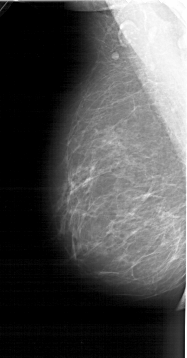

A_1403_1.RIGHT_MLO

LEFT_MLO LINES 6436 PIXELS_PER_LINE 3361 BITS_PER_PIXEL 12 RESOLUTION 43.5 NON_OVERLAY